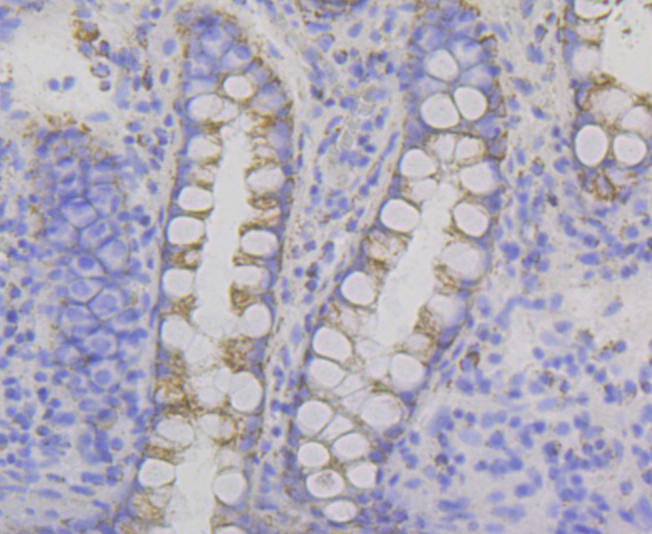

Immunohistochemistry analysis in human spleen and endometrium tissues using Anti-P2RY6 antibody. Corresponding P2RY6 RNA-seq data are presented for the same tissues.

TargetP2RY6

- Target nameP2RY6

- Target descriptionpyrimidinergic receptor P2Y6